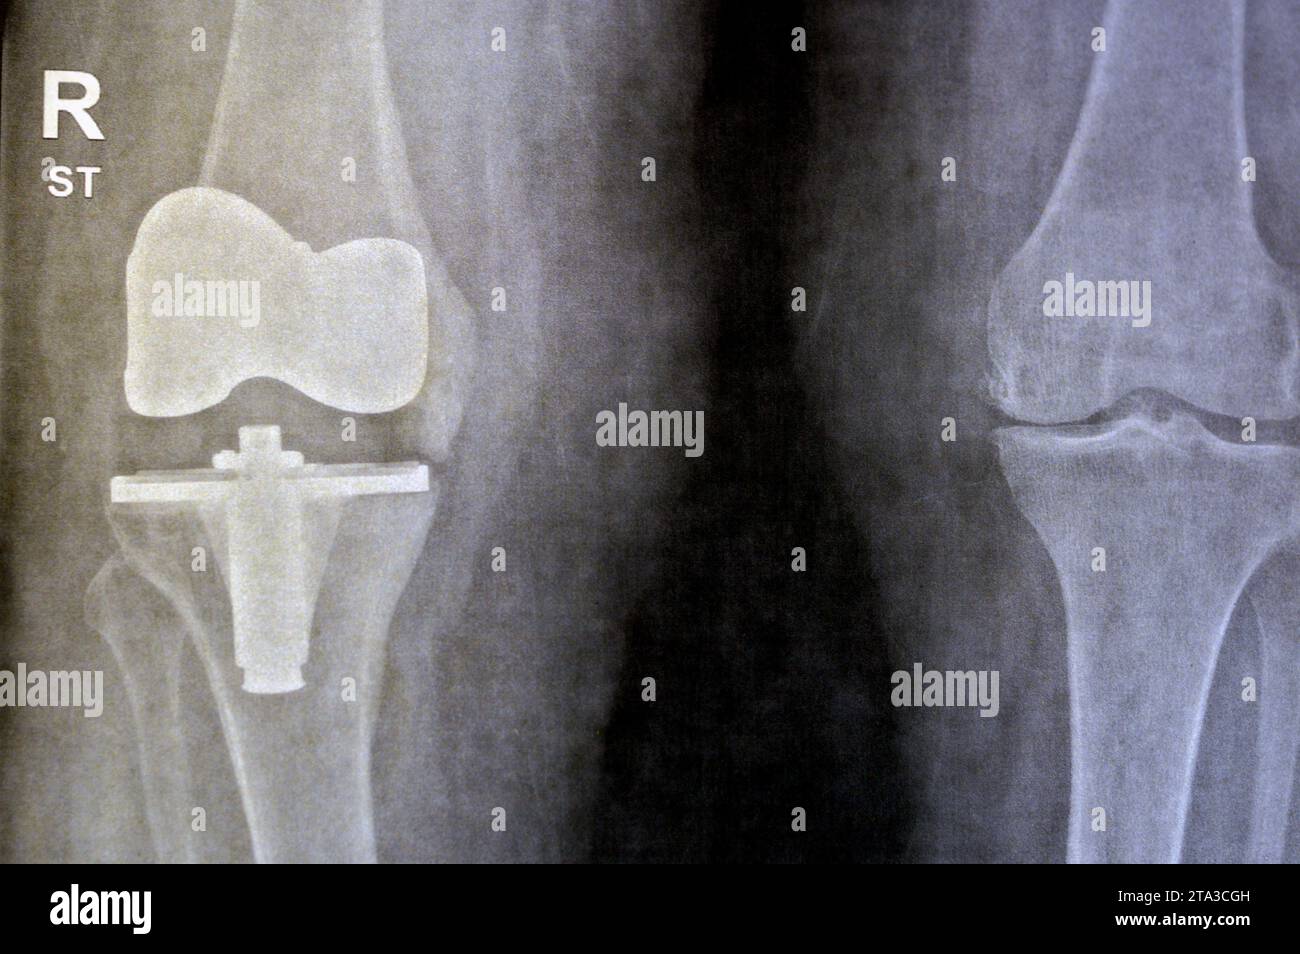

Plain Xray of knee joints, right side shows total knee replacement When To Replace A Knee Joint Is it the right time to have a knee replacement? The main reason to have it done is pain. It can be either a total knee replacement (tkr) or a. During a total knee replacement (tkr), the bone and cartilage at the end of the thigh bone and shinbone are removed. A knee replacement is an operation to replace damaged. When To Replace A Knee Joint.

Plain Xray of knee joints, right side shows total knee replacement When To Replace A Knee Joint During a total knee replacement (tkr), the bone and cartilage at the end of the thigh bone and shinbone are removed. The whole knee is replaced. It’s a type of procedure called an arthroplasty (joint replacement). Is it the right time to have a knee replacement? A knee replacement is surgery to replace all or some of your knee joint.. When To Replace A Knee Joint.